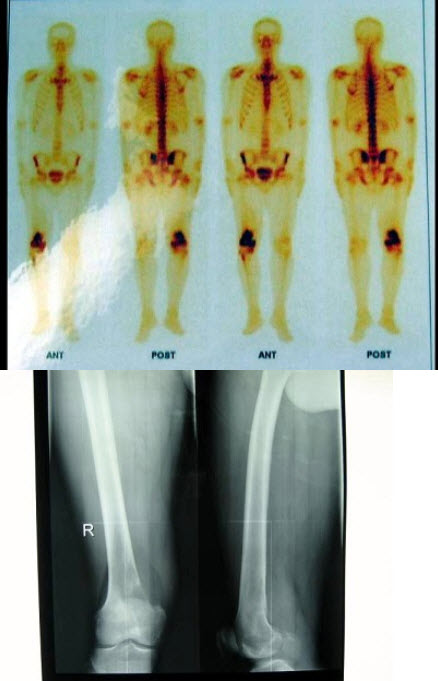

107、单项选择题

男性,29岁,右侧下肢疼痛3个月,行X线片及骨显像检查,正确的诊断是()

A.右侧下肢膝关节炎

B.右侧股骨下端成骨性骨肉瘤

C.右侧股骨下端溶骨性骨肉瘤

D.右侧股骨下端骨纤维肉瘤

E.以上都不是